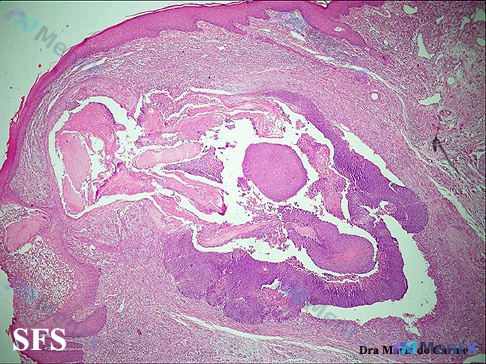

最近看到一张皮肤病理的显微镜下影像,整理一下思路和大家讨论,很容易一开始就锚定在常见囊肿上,但有个细节值得警惕。 先看影像里的核心表现 1. 组织结构:表皮相对完整,真皮内有一个巨大的囊状扩张结构,囊腔内充满大量嗜伊红染色的均质/板层状物质,形态很像角蛋白。 2. 囊壁与细胞:囊壁是复层鳞状上皮,细...